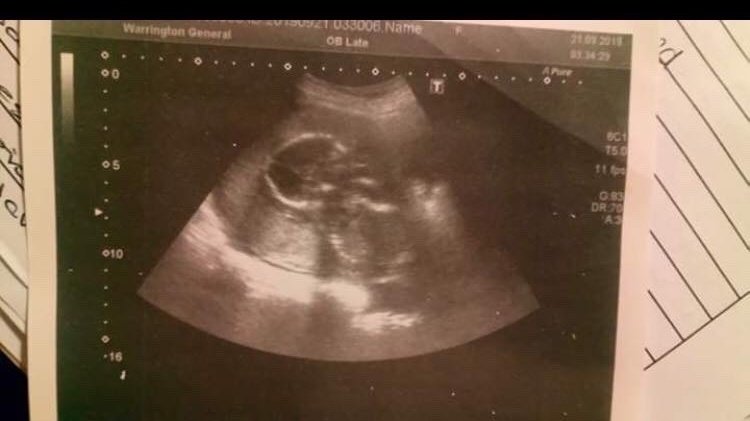

The law doesn’t see your child as a person until 24 weeks. A childs heart starts beating 22 days after conception, the heart beat is visible onscreen after 5 weeks, by 16 weeks you can find out the babies sex. Children should be recognised as life when their heart starts beating, the gestation time stated in the law should be moved to 16-18 weeks as that is when a baby stops being an “it” and starts becoming a “he” or a “she” this is when babies start becoming an individual and so this is when babies should be recognised as life. A new legislation needs to be put into place to protect those lives that can not yet protect themselves. So many mothers don’t get the privilege of raising the child that grew inside them due to no fault of their own, its a privilege every mother deserves and yet not every one gets to have.